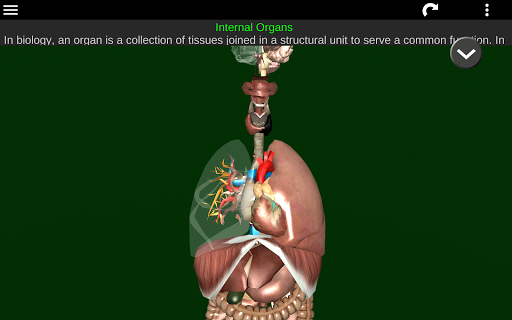

Menampilkan model anatomi 3D dari organ utama tubuh manusia dan penjelasannya masing-masing.

* Sistem pencernaan, termasuk lambung, usus kecil, usus besar, dan animasi sistem ini.

* Sistem pernafasan, yang meliputi trakea, bronkus, paru-paru dan animasi sistem ini.

* Otak, yang meliputi otak, otak kecil, dan batang otak.

* Jantung, yang meliputi atrium, ventrikel, aorta, dan animasi organ ini.

* Mudah diakses dan dinavigasi (zoom, rotasi 3D).

* Sembunyikan atau tampilkan informasi.